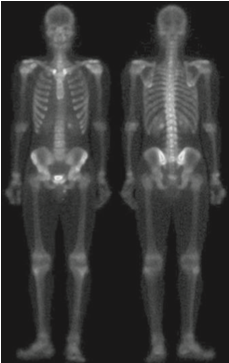

실제로 일반적인 샤프닝 영상에 비해서 훨씬 깔끔한 영상을 얻은 것을 볼 수 있습니다. 하지만 여전히 밝기값이 낮기 때문에 마지막으로 거듭제곱-법칙 변환을 적용해여 아래의 최종 영상을 얻을 수 있습니다.